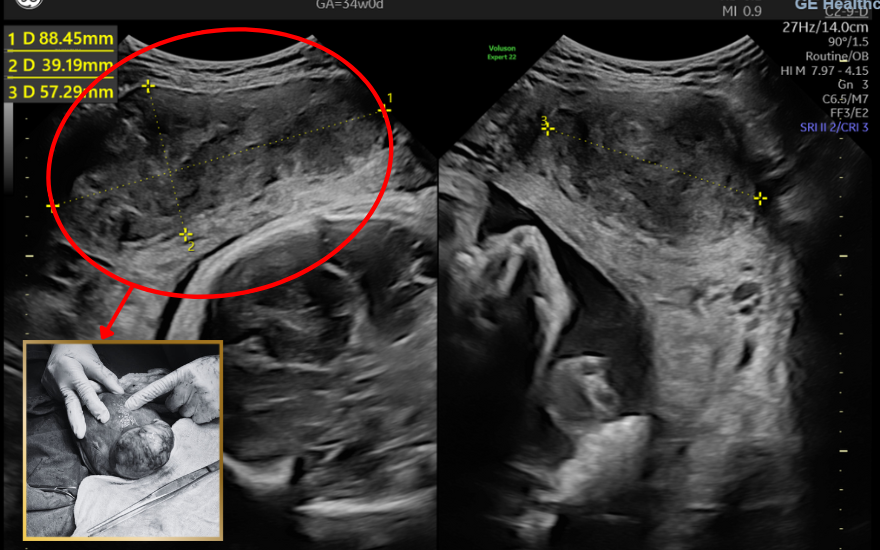

Càng về những tuần cuối thai kỳ, khối u xơ tử cung lại càng phát triển nhanh. Đến tuần thứ 38, khối u đã có kích thước tới 50x48x89mm. Nhận định đây là “thời điểm vàng” để mổ bắt con khi em bé đã phát triển đầy đủ, sức khỏe mẹ ổn định và khối u chưa gây ra triệu chứng gì nặng nề nên các bác sĩ đã nhanh chóng thực hiện theo đúng kế hoạch cho ca mổ đầy khó khăn này.

Hình ảnh siêu âm và thực tế khối u xơ tử cung khi mổ lấy thai.